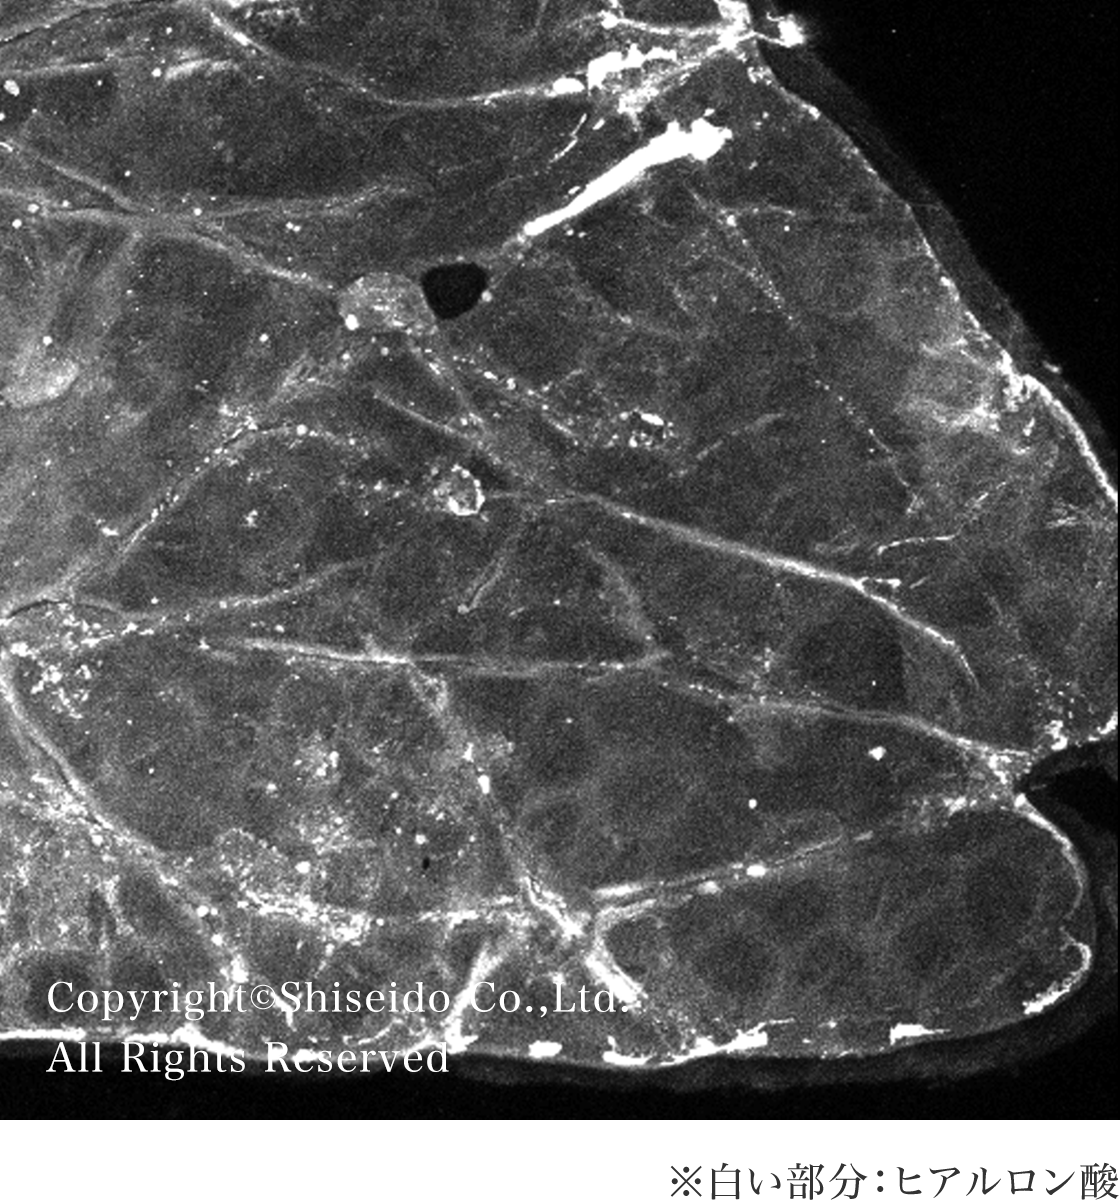

生体内にも存在するヒアルロン酸は加齢により減少することが知られており、まぶたの皮ふでもヒアルロン酸が減少していることが確認されています。

ヒアルロン酸量の比較 (日光に露出した瞼の皮膚で実験)

引用元:S. Iiryama et al., Am J Pathol. 191(6):1010-1019, 2021(グラフ一部改変)